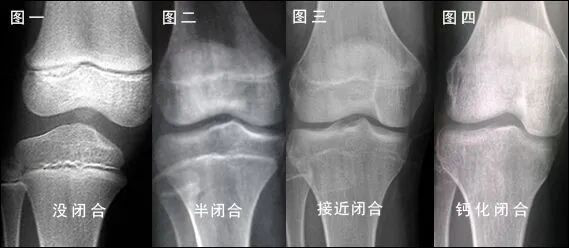

骨骺线就是骨骺和干骺端中间的软骨,从X光上来看,会看见一条透光细缝。在发育期的孩子,当骨骺和干骺端的软骨完全骨化以后,就代表发育完成,骨骺线就会闭合不见,这个时候孩子们就停止发育,不会再长高了。

作为家长的您还记得吗?我们自己在上学的时候,长高一段时间后,突然就不再长了,那可能就是骨骺线闭合了。因此,决定身高的“关键因素”就是在骨骺线闭合之前,让孩子抓紧时间长高!

身高生长停止的标志是

骨骺和骨干完全融合成长板消失

男童约为骨龄16岁

女童约为骨龄14岁

身高是否还有增长的空间,是评价大年龄儿童手骨片首先可以了解的。根据手骨片上成长板是否存在、成长板数量的多少、成长板缝隙的形状,基本可以确定一个孩子还有多少长高的潜能。